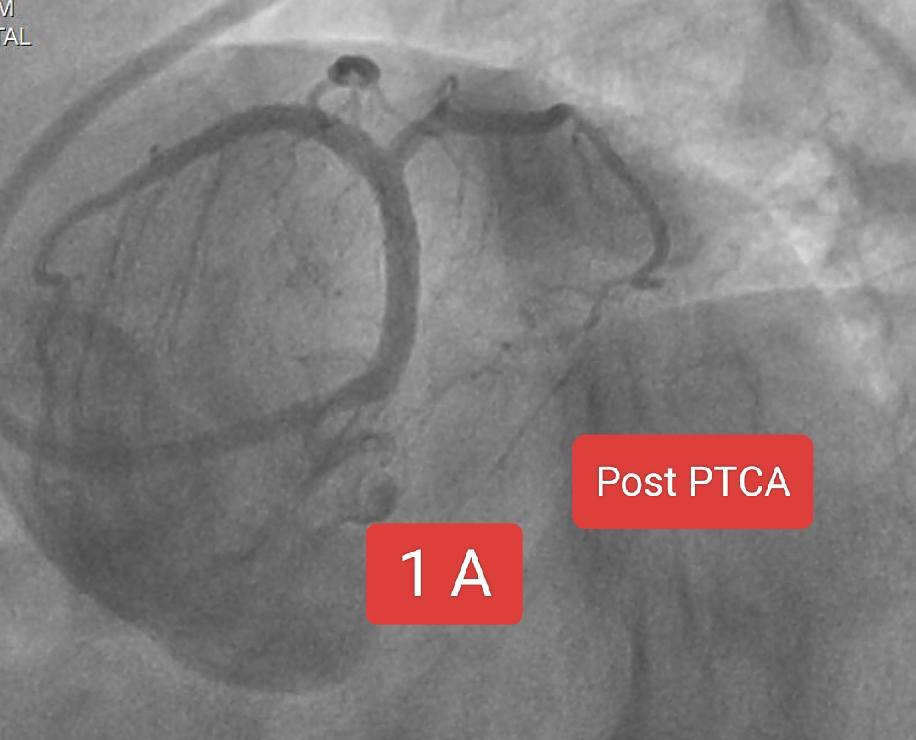

60 year old male patient presented with acute onset chest pain since 2 hours. ECG SHOWED inferior wall STEMI ECHO showed No RWMA , Normal LV SYSTOLIC function The timing of intervention is absolutely critical when performing Primary PTCA for a patient with STEMI. This is because heart muscle (myocardium) begins to die within minutes after a coronary artery is occlude. The longer the delay, the more myocardial tissue is irreversibly damaged. The ideal goal is a door to balloon time 90 minutes (from hospital arrival to inflation of the balloon). Each 30-minute delay increases 1-year mortality by up to 7.5%. In this case we successfully managed to shift the patient to lab with 15 minutes of arrival. Angiogram showed 100% thrombotic cut off in mid RCA. Wiring and successful thrombosuction was followed by prompt stenting all within 15 minutes of arrival to cath lab.